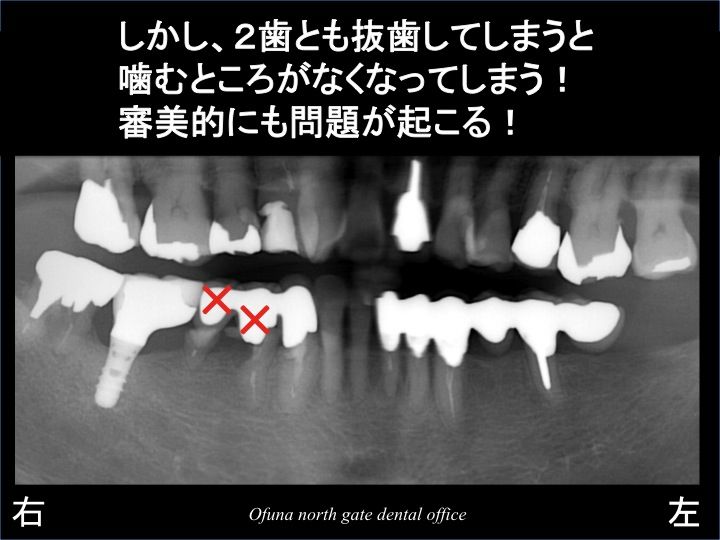

次に問題となったのが、抜歯後の治療の進め方です。

2歯とも抜歯してしまうと 当然のことながら 欠損してしまいます。

患者様は、治療期間中に歯がないことは嫌とのことでした。

また、義歯(入れ歯)を使用することもご希望されませんでした。

難しいご要望です。

どのようなことが患者様にとって良いのか?

を考えました。

そして以下のような治療計画を立てました。

とりあえず、奥の1歯のみ抜歯します。

治療期間中は、取れたセラミック(3歯連結された被せ物)を仮歯として使用します。